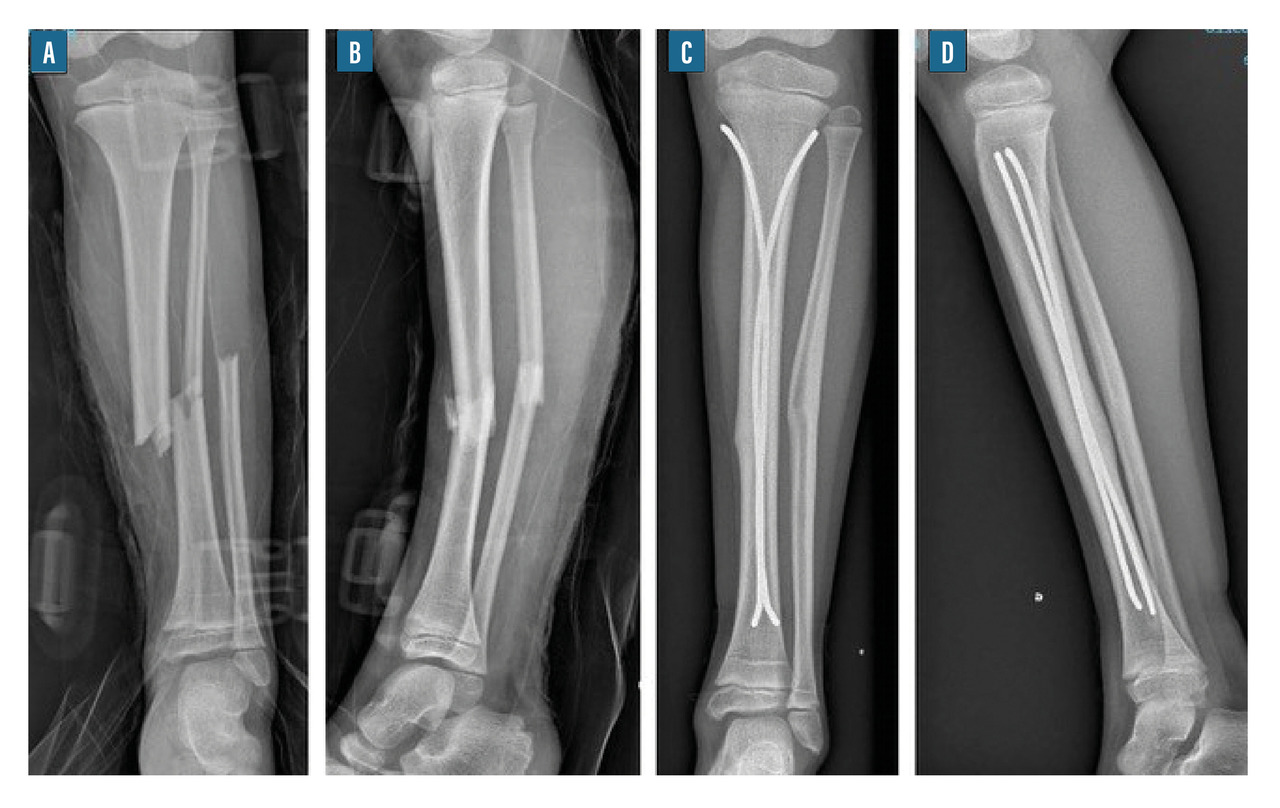

• l’embrochage centromédullaire élastique stable (ECMES) est une méthode couramment utilisée en traumatologie infantile. Elle consiste à mettre des broches cintrées et béquillées dans le canal médullaire et obtenir ainsi une stabilité élastique du foyer (fig. 10). Toute force appliquée sur l’os provoque un déplacement avec retour élastique à l’état d’équilibre qui est l’état anatomique ;12